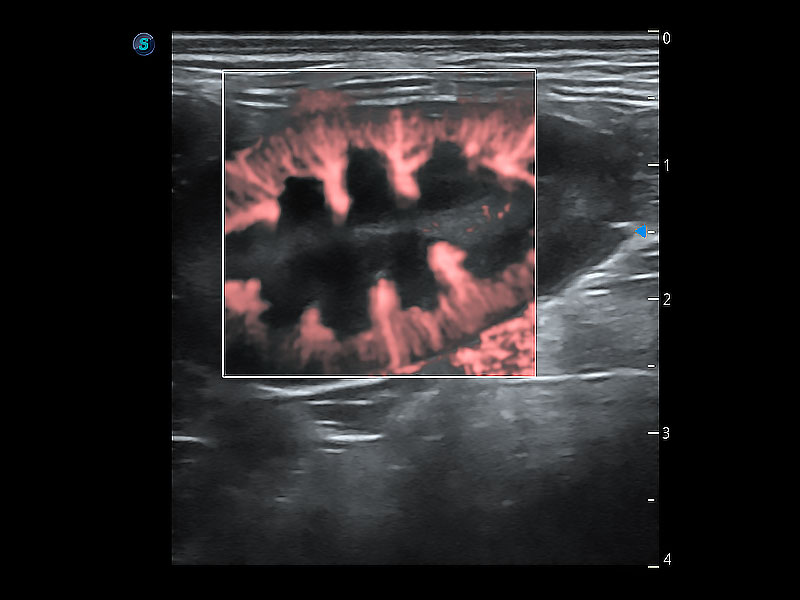

(犬)肾脏显微血流

• Micro F 显微血流成像

极大提升超低速微细血流的检出能力,同时更精准地滤除软组织和超声信号,为兽用医生提供以往无法通过常规血流获得的疾病诊断信息。

优异的基础图像

ProPet 80 全新的动物超声智能软件和丰富的探头群,为动物医生提供了高清晰度和精细分辨率的图像,无论在宠物、马科、畜牧还是实验室动物等应用中都可以轻松应对,为您的日常工作带来满意的体验。